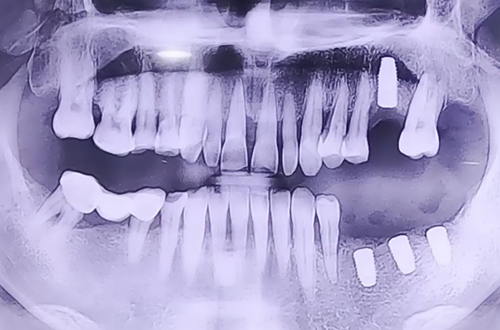

위/아래 어금니 임플란트

BEFORE

왼쪽 위, 아래 어금니가 거의 없어서 오른쪽 치아로만 식사를 하셔야 하는 불편함을 호소하며 내원해 주셨던 환자분이십니다.

발치한 부분의 잇몸 상태나 주변 치아 상태를 꼼꼼히 확인하고 임플란트 식립하였으며, 추가 발치나 뼈이식이 필요한 부분에도 조치를 시행해 드렸습니다.

약 4개월 정도 임플란트가 단단히 자리 잡힌 뒤 예쁘게 보철을 씌워드릴 때 다음 진료일지로 뵙겠습니다! ^^